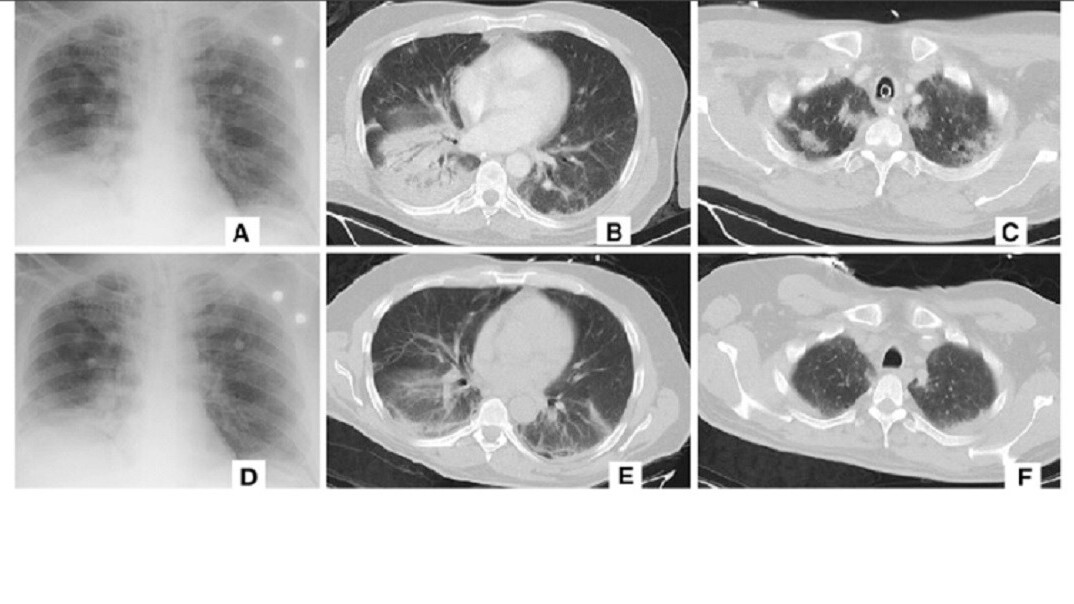

Per a report from Nikkei’s Asian Review (h/t TechSpot), Alibaba claims its new system can detect coronavirus in CT scans of patients’ chests with 96% accuracy against viral pneumonia cases. And it only takes 20 seconds for the AI to make a determination – according to the report, humans generally take about 15 minutes to diagnose the illness as there can be upwards of 300 images to evaluate.

The system was trained on images and data from 5,000 confirmed coronavirus cases and has already been tested in hospitals throughout China. According to the Review’s report, at least 100 healthcare facilities are currently employing Alibaba’s AI.